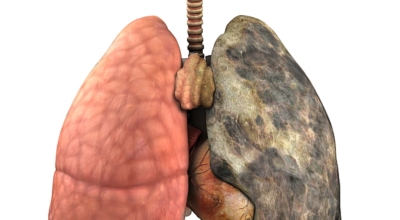

폐암의 가장 큰 원인이며, 폐암 환자의 80-90%가 흡연에서 비롯될 수 있다고 할 수 있어요. 흡연을 자주 할 시 폐암 발생 위험이 흡연을 하지 않은 사람보다 13배가 증가를 할 수가 있고, 간접흡연 역시 1.5배나 폐암 걸릴 확률이 있어 흡연은 폐암 그 자체라고 생각하시면 될 것 같아요.

가족력으로 폐암에 걸릴 수가 있어요. 친척 포함 가족력 역시 폐암을 무시할 수가 없는데 가족 중 폐암을 가지고 있는 사람이 있을 경우 2~3배 발병률이 높는 것으로 알려져 있어요. 마지막은 생활환경이지요. 흡연 외에도 가스, 미세먼지, 암 유발 물질 노출, 대기오염 과 같은 생활환경에 따라 폐암이 발생할 수 있어요.